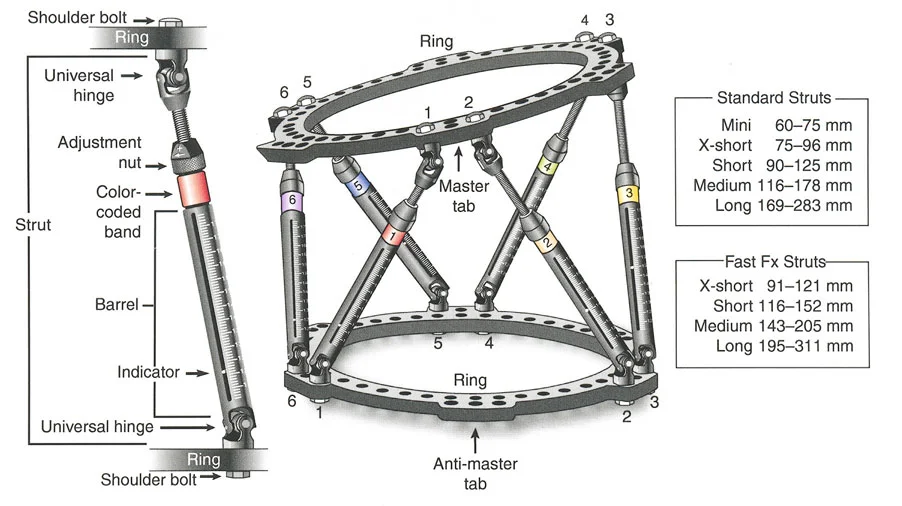

- مثبتات إليزاروف الدائرية الكلاسيكية: تتكون من حلقات معدنية متصلة بالعظم بأسلاك رفيعة، وتسمح بتصحيح متعدد المستويات.

- أنظمة الهيكسابود الحديثة (مثل جهاز تايلور الفراغي Taylor Spatial Frame): تستخدم ست دعامات متداخلة (struts) متصلة بحلقتين. يتم التحكم فيها بواسطة برنامج حاسوبي يقوم بحساب التعديلات اليومية بدقة فائقة لتصحيح التشوه في ستة اتجاهات.

- المثبتات أحادية الجانب (Monolateral Fixators): تتميز بقضيب واحد يمتد على طول الطرف، وتستخدم غالبًا للتصحيحات الخطية أو الزاوية البسيطة.